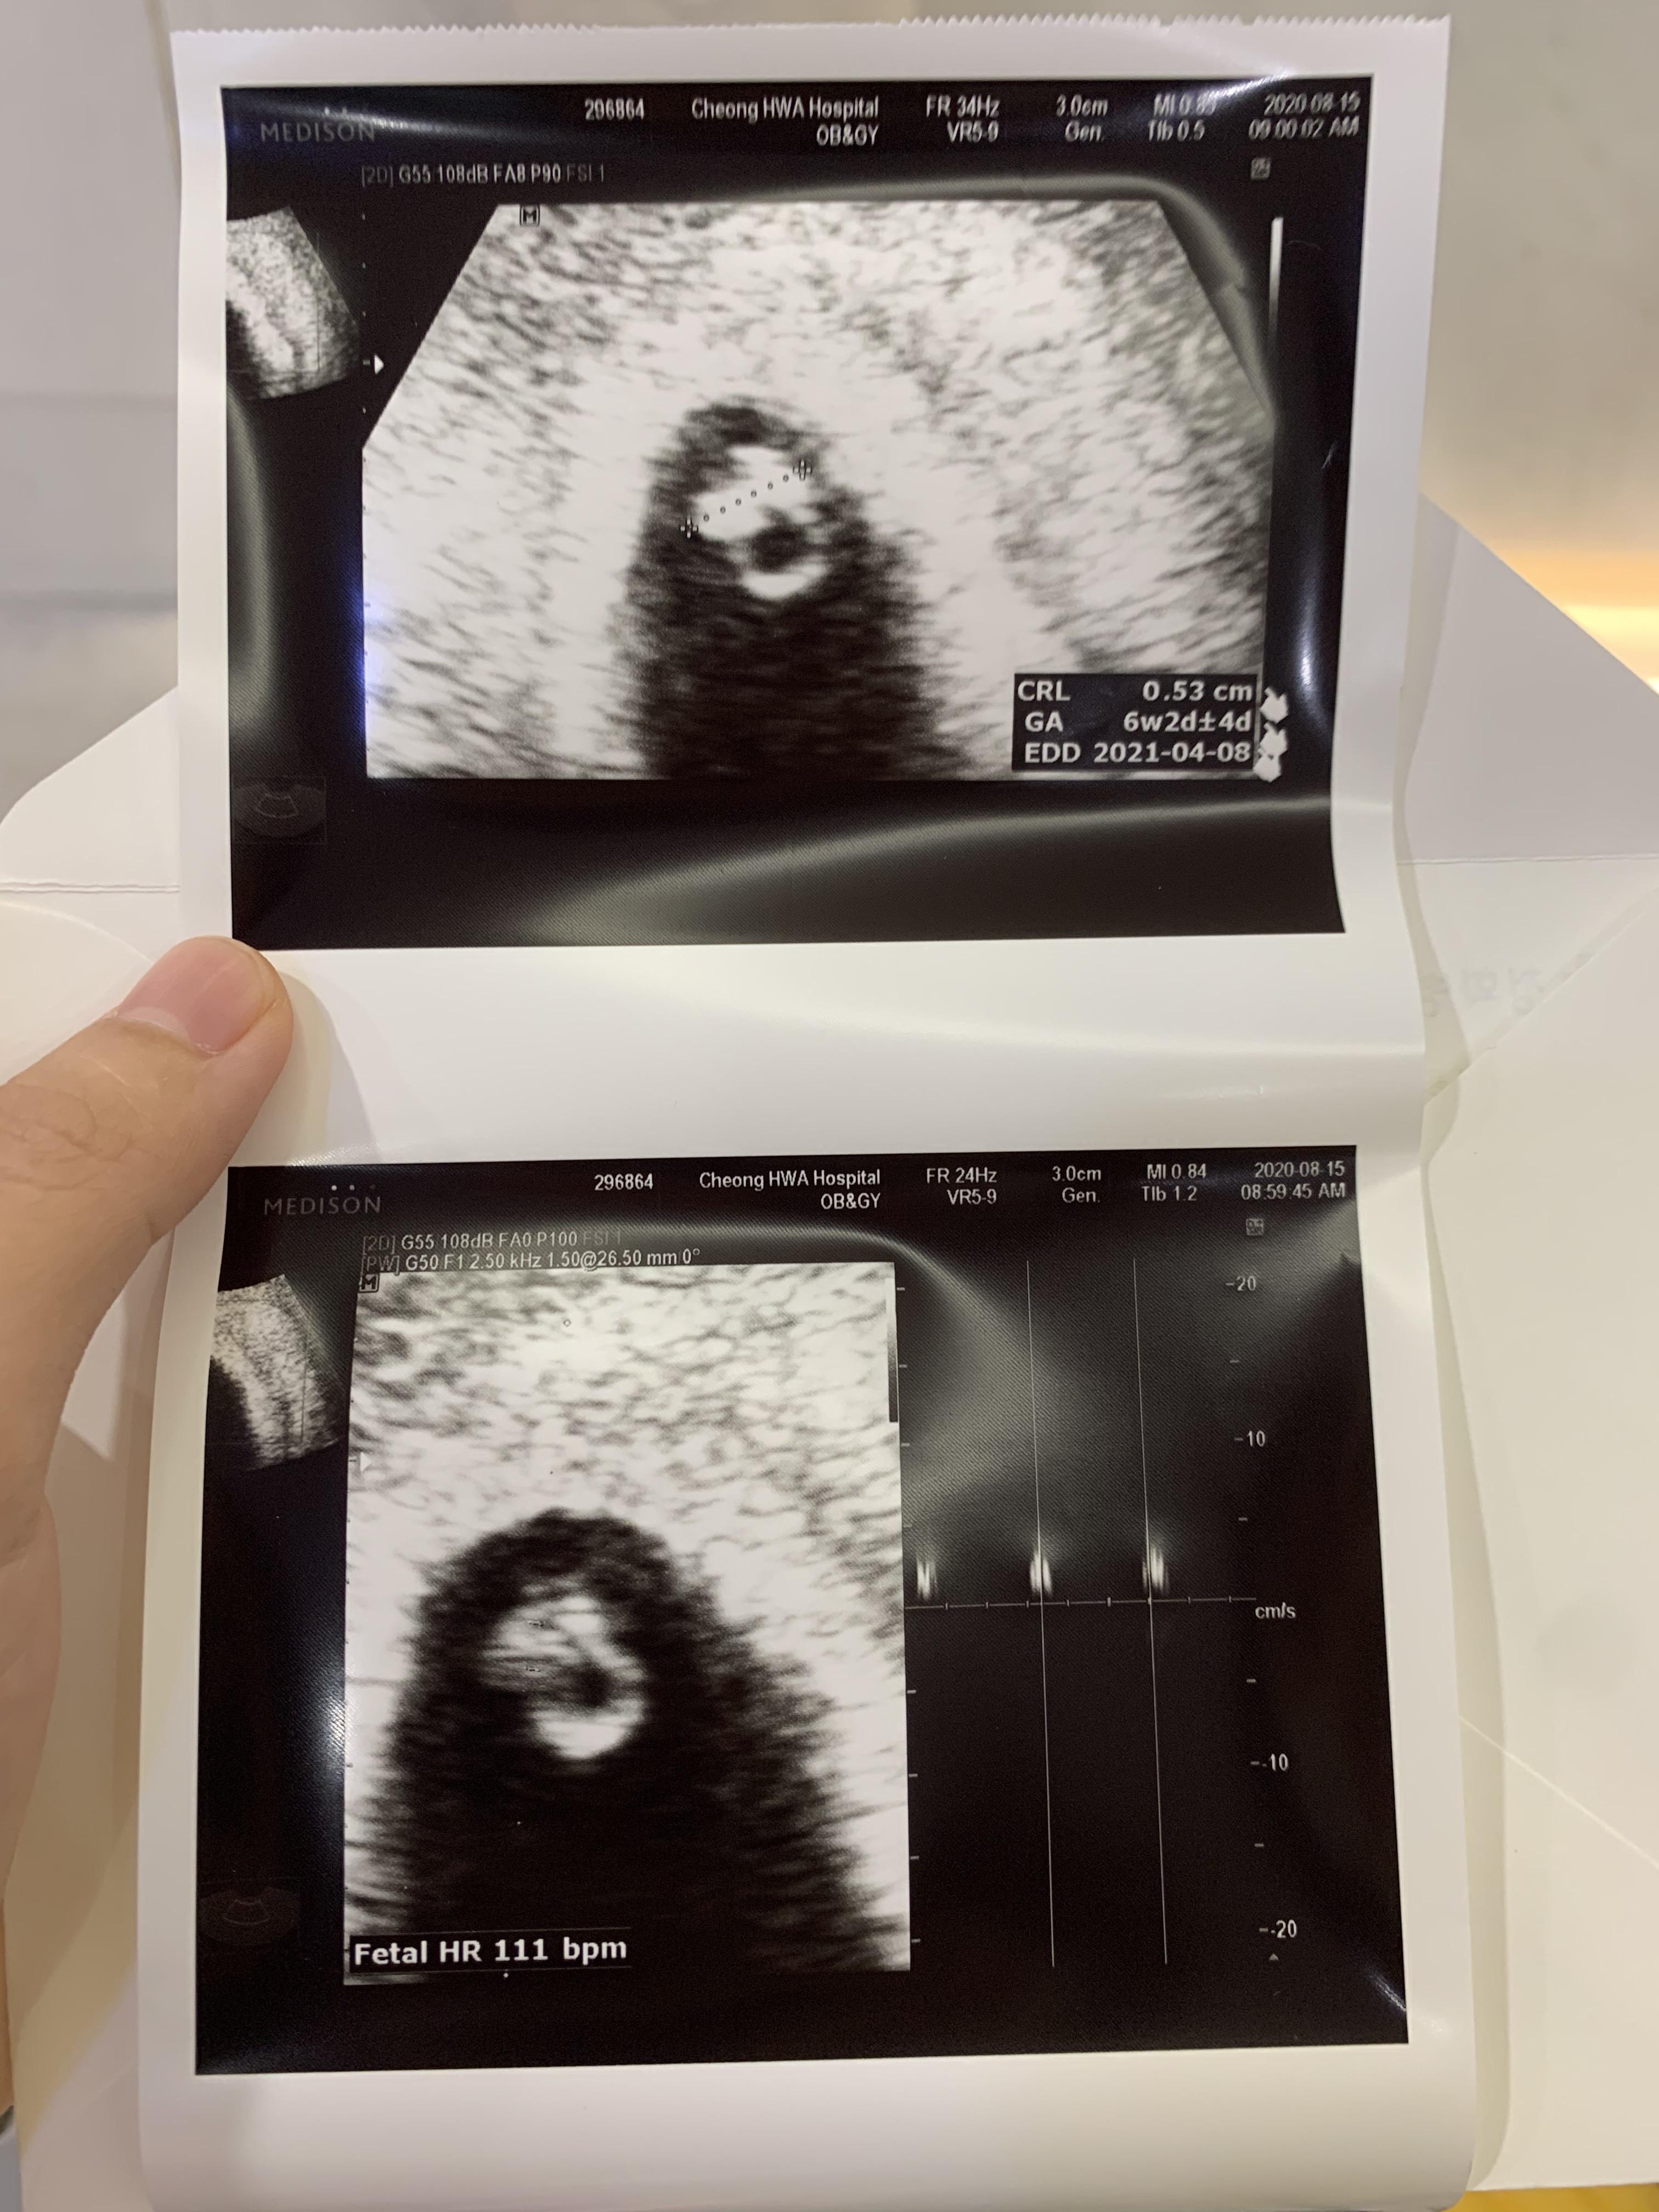

난황에 배아까지 봅니다!

게다가 반짝반짝 심장소리까지 들었어요!

아기집은 두 배로 커져서 2센티 정도 되고,

아기 크기가 0.5cm정도 되더라고요.

심장소리 츄큐츄큐 111bpm

추정 주수는 6주로 알고 갔는데, 3일 빨라진

6주 3일로 확인하고 돌아옵니다.

심장소리는 111bpm으로 들었는데,

정상범위인지 궁금해서 또 찾아봤지요.

6주차 추정 시기에는 103-126 이 범위래요.

이렇게 또 감사하게 정상 범위에 안착!